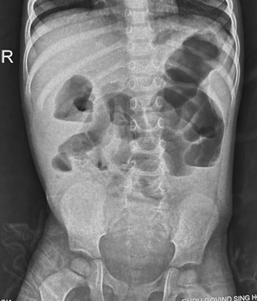

However, in small bowel obstruction, there is too much gas in the small bowel loops compared to the colon. Conversely, in colon obstruction with intact ileocecal valve, there is too much gas in the colon (Figure 3) compared to the small intestine and there is little or no gas in the rectum.5 The lack of gas in the rectum, however, is a late sign of bowel obstruction, so patients who present early in their disease process may have gas in the rectum on radiograph.

Figure 3 Anteroposterior supine abdominal radiograph in a 4-year-old child showing dilatation of bowel with smooth walls with too much gas in colon (haustra can be seen to identify colon) and absence of gas in the rectum suggestive of distal large bowel obstruction at level of rectosigmoid junction probably due to Hirschsprung’s disease.

In older children, like adults, the small bowel is centrally located, framed by the large bowel. The small bowel's mucosal folds, called valvulae conniventes, are visible across the full width of the bowel. The large bowel has pouches or sacculation called haustra that protrude into the lumen. Haustra are thicker than valvulae conniventes and typically do not appear to completely traverse the bowel (Figure 3). If the dilated bowel loops exhibit valvulae conniventes, it indicates involvement of the small intestine. Conversely, if they show haustra, it suggests involvement of the colon.

In colon obstruction, air fluid levels are not present because water is absorbed in colon (Figure 3).